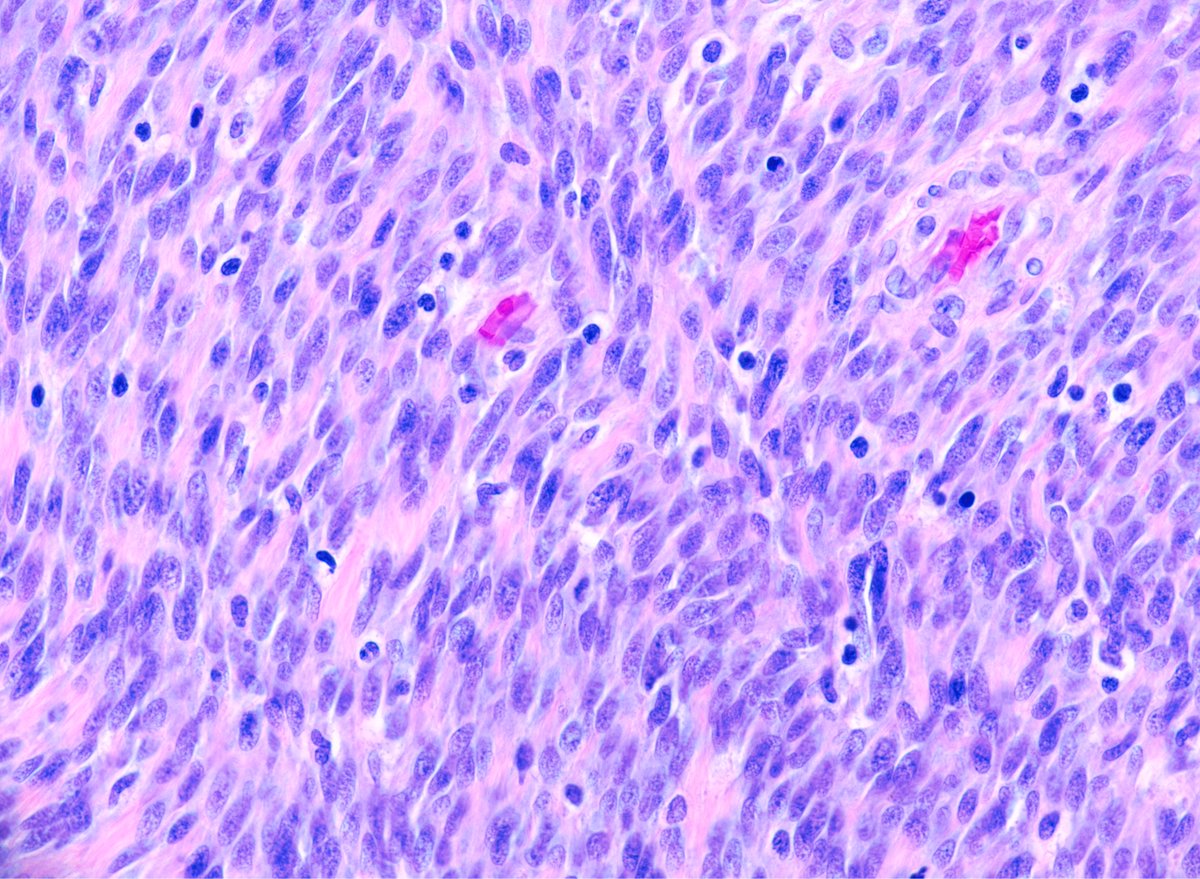

Spindle Cell Rhabdomyosarcoma Molecular . This neoplasm contains relatively differentiated spindle cells having cytologic. The evolving classification of rhabdomyosarcoma (rms) now includes spindle cell rms (srms). Historically, these tumors have been variably diagnosed as the spindle cell variant of erms or spindle cell rms, but they are more. Spindle cell rhabdomyosarcoma (type a lesion). The spindle cell variant of rhabdomyosarcoma (srms) is an uncommon subtype of rms that was initially grouped under erms, having. Three genomic groups have been defined:

Spindle cell rhabdomyosarcoma (type a lesion). Historically, these tumors have been variably diagnosed as the spindle cell variant of erms or spindle cell rms, but they are more. Three genomic groups have been defined: This neoplasm contains relatively differentiated spindle cells having cytologic. The evolving classification of rhabdomyosarcoma (rms) now includes spindle cell rms (srms). The spindle cell variant of rhabdomyosarcoma (srms) is an uncommon subtype of rms that was initially grouped under erms, having.

Spindle cell/sclerosing A. Fusiform morphology of Spindle Cell Rhabdomyosarcoma Molecular This neoplasm contains relatively differentiated spindle cells having cytologic. Historically, these tumors have been variably diagnosed as the spindle cell variant of erms or spindle cell rms, but they are more. Three genomic groups have been defined: The evolving classification of rhabdomyosarcoma (rms) now includes spindle cell rms (srms). The spindle cell variant of rhabdomyosarcoma (srms) is an uncommon subtype. Spindle Cell Rhabdomyosarcoma Molecular.

Spindle cell light micrograph Stock Image C049 Spindle Cell Rhabdomyosarcoma Molecular This neoplasm contains relatively differentiated spindle cells having cytologic. Historically, these tumors have been variably diagnosed as the spindle cell variant of erms or spindle cell rms, but they are more. Spindle cell rhabdomyosarcoma (type a lesion). Three genomic groups have been defined: The spindle cell variant of rhabdomyosarcoma (srms) is an uncommon subtype of rms that was initially grouped. Spindle Cell Rhabdomyosarcoma Molecular.